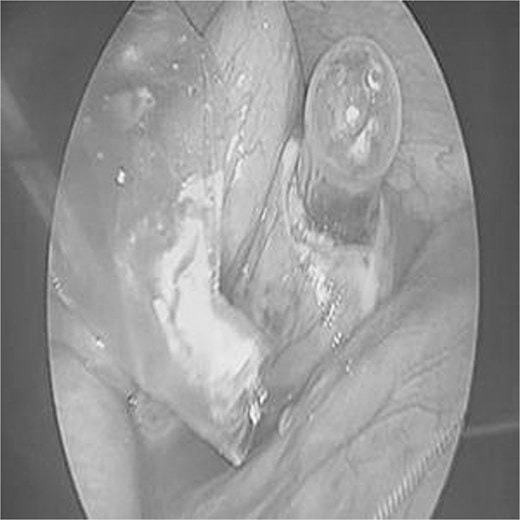

Theo Need To Know, một cuộc nội soi khẩn cấp đã phát hiện ra vật thể bị kẹt và các bác sĩ phải phẫu thuật lấy ra, sau đó khâu lại vùng bị kẹt .

Cùng lúc đó, ruột thừa của đứa trẻ cũng được cắt bỏ, mặc dù người ta không tin rằng nguyên nhân là do đứa trẻ nuốt phải núm vú của bình sữa.

Một bức ảnh được các bác sĩ chia sẻ trong báo cáo y khoa cho thấy núm vú đầy đủ kích thước và phần ruột thừa sau khi được cắt bỏ.